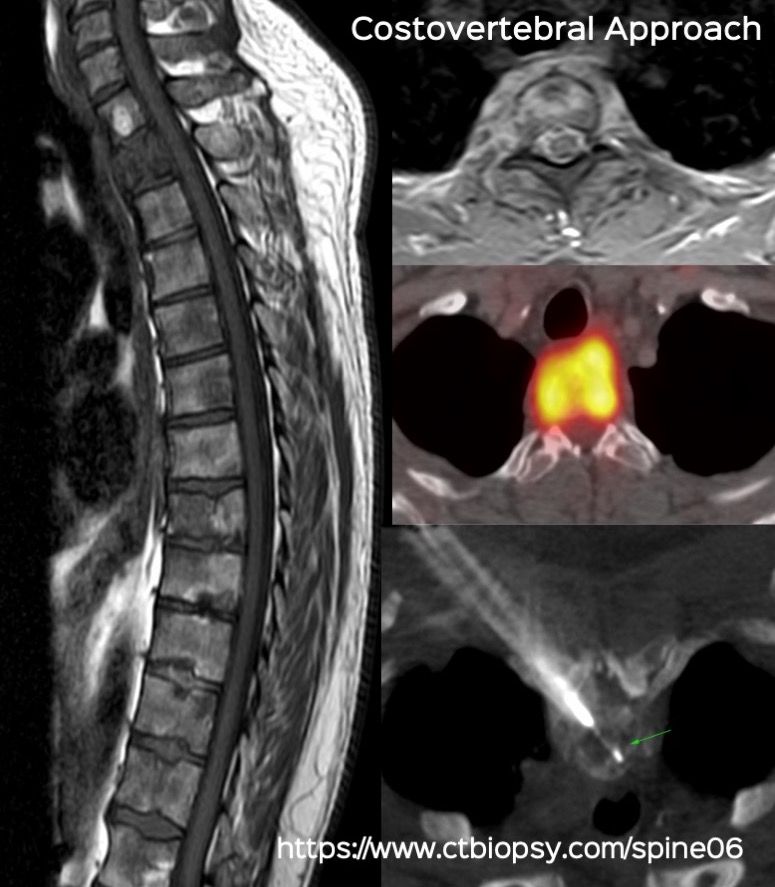

Case 73: The Costovertebral Approach for Dorsal Vertebral Body Biopsies